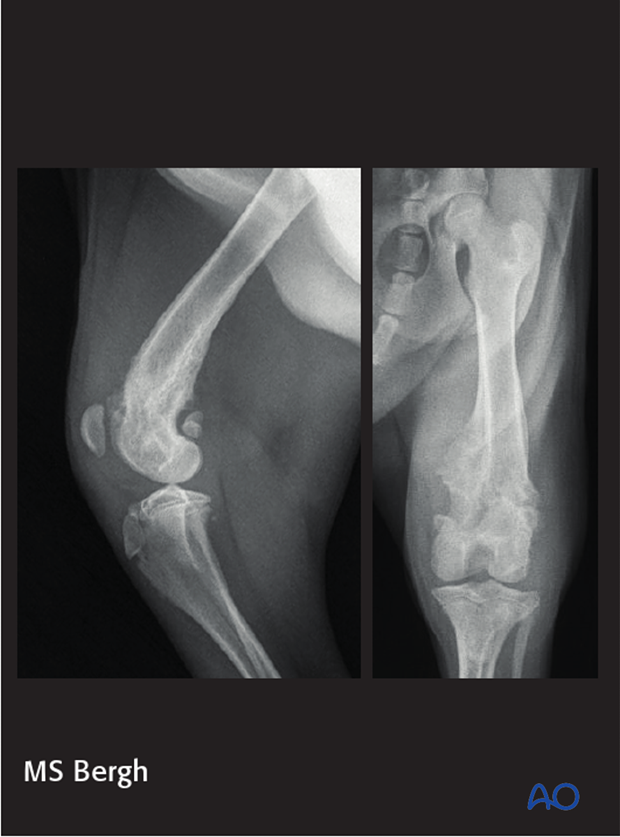

The radiographs show a malunion of a distal femoral fracture in a 3-year-old mix breed that was managed non-surgically. The condyles are under reduced and the metaphyseal segment is impinging on patellar tracking. In addition, there is marked femoral valgus. Function of the limb was poor.